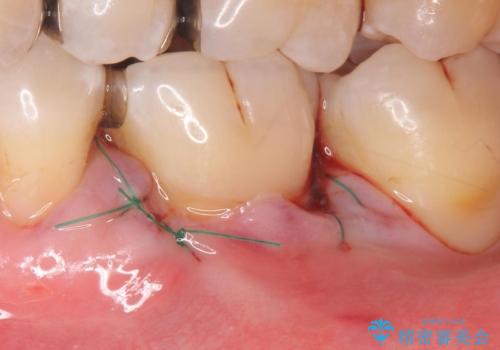

- 奥歯の歯茎が下がっていて(歯肉退縮)歯が染みるとのことで来院された患者様です。

退縮した歯茎に対して移植をすることで、しみる場所を覆う計画です。

歯根の分岐部よりも根尖側の頬側面が露出している状態でしたが、露出部位を分岐部までに抑えることができました。

しみる症状も改善され、大変喜んでいただけました。